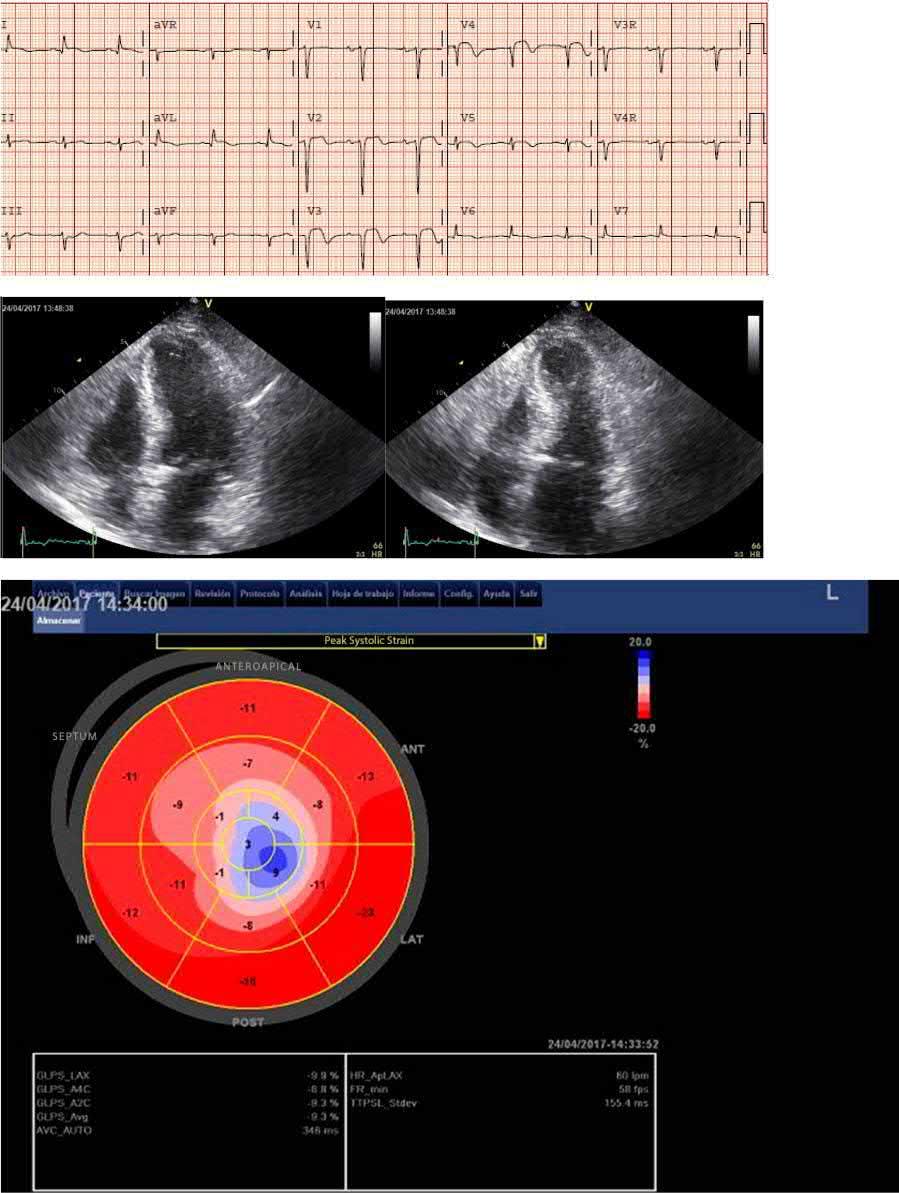

Figure 1.2 ECG‐echocardiography correlation. Post‐reperfusion ECG of an 82‐year‐old patient with LAD occlusion. The ECG shows anteroapical STE‐ACS. There is ST‐segment elevation in I and aVL: although the occlusion was in the mid‐LAD, there was one or more diagonal branches distal to the occlusion (Eskola et al. 2007) End‐diastolic (left) and end‐systolic (right) apical long‐axis views show hypokinesia of the apex and compensatory hyperkinesia of the basal septum and lateral wall. Strain rate imaging (bull’s eye) clearly delineates the region with apical dyskinesia (see Plate 2 in color plates).

A 70‐year old woman with a 2‐day history of malaise, weakness, nausea, and vomiting. She reported crushing chest pain with dyspnea on effort, which subsided with rest, for several weeks. The ECG in the emergency department showed anterior ST elevation with right bundle branch block and left anterior fascicular block. Coronary angiography showed a subtotal occlusion of the proximal LAD with TIMI

1 flow. Primary PCI was performed with implantation of a drug‐eluting stent. The post‐reperfusion ECG (Figure) shows persistence of the ST elevations and conduction disorders. Despite reperfusion therapy, there was hemodynamic instability and metabolic acidosis with need for vasoactive support with noradrenaline. Echocardiography showed septal hypokinesis.

The persistence of ST elevations and hemodynamic instability should raise the suspicion of a post‐infarction mechanical complication. The echocardiogram should be repeated in several projections. Next figure shows a rupture of the interventricular septum (arrow) that had gone unnoticed. In this case the ECG pattern was an important key to raise the suspicion of an important complication of the disease.